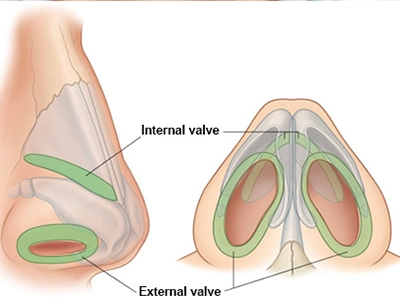

ترمیم دریچههای داخلی/خارجی بینی برای جلوگیری از کلاپس هنگام دم

جراحی زیبایی بینی (رینوپلاستی) تنها با هدف تغییر ظاهر انجام نمیشود؛ یکی از ارکان مهم موفقیت آن، حفظ یا بهبود عملکرد تنفسی است. پیش از عمل، ارزیابی دقیق مسیرهای تنفسی توسط جراح انجام میشود تا هرگونه انسداد، انحراف تیغه یا تنگی دریچههای بینی مشخص شود.

بررسی داخل بینی با آندوسکوپی برای مشاهده دقیق دریچهها و شاخکهای بینی

ترکیب دقت در تحلیل زیبایی و ارزیابی عملکرد تنفسی باعث میشود نتیجه نهایی نهتنها از نظر ظاهری طبیعی و متناسب باشد، بلکه تنفس بیمار نیز بهبود یابد و از بروز عوارضی مانند گرفتگی یا تنگی مسیر هوا جلوگیری شود.